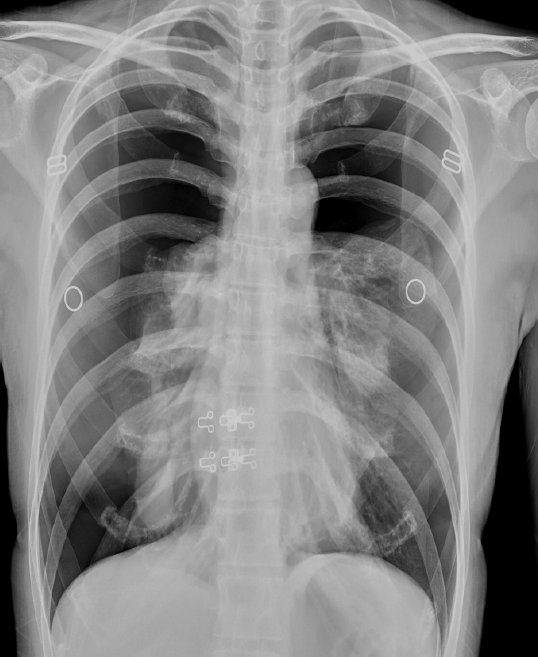

32歲女性,於2024年6月來診,主訴早上開始覺得呼吸喘及胸痛治急診就醫,檢傷生命徵象:體溫36.8∘C,心跳114下/分鐘,呼吸24下/分鐘,室氧下濃度86%,血壓171/78mmHg。病人過去病史為在2019年前曾因子宮內膜異位瘤手術,術後持續接受荷爾蒙治療(Dienogest)直到2023年,約一個月前因不孕症開始嘗試IVF。理學檢查時發現雙側呼吸音減低,胸腔X光(圖一)發現雙側氣胸,經雙側胸管置放後呼吸喘狀況改善。後續的胸腔電腦斷層時發現右側橫膈膜節結(圖二),懷疑子宮內膜異位造成經期性氣胸,安排雙側video-assisted thoracoscopy (VAT),並進行雙側病灶處wedge resection及肋膜沾黏術,術後病理切片顯示為子宮內膜異位組織,出院後病人至婦產科門診持續接受子宮內膜異位的賀爾蒙治療(Dienogest)。

圖一、(左側) 胸腔X光:雙側氣胸。

本圖取自臨床圖片,去病人資訊授權重製經期性氣胸